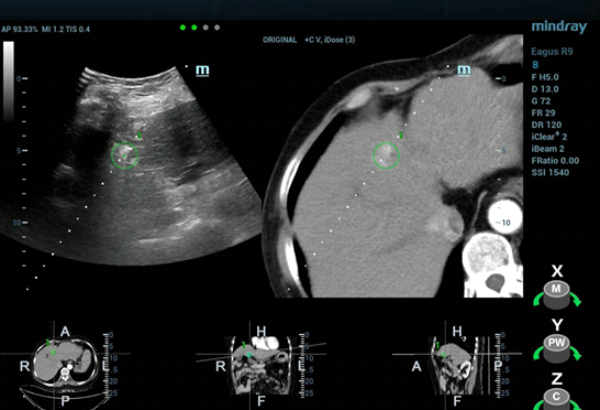

CT??? ??? S4?? ??? ??? ?? ???????? ??? ?????. CEUS(Contrast-Enhanced Ultra Sound)????? ?????? ??? ??? ??? ??? ???? ? ??? ???? ???? ??? ???????.

??? ??? ?? ????? ???(MWA)? ?? ?????? ?? ?????? ??? ???? ??? ?? Contrast-enhanced CT? ???? ??? ?? ??? ??? ?? ??? ?? ??? ????? ???? ???? ????? ??(MWA)? ??? ???????.

??? ????? ??? 2D ??? ??? ???? ???? ???? ??? ? ????? ??? ??? ?? ?????? ???? ?? ??? ???? ???? ??? ? ?????. ??? ??? ???? ??? ?? CT ??? ??? ???? ??? ??? ??? ?? MWA? ?? ???? ??? ???? ?????. CEUS(Contrast-Enhanced Ultra Sound)? ???? ?? ? ??? ??? ????, ?? ? ?? ??? ???? ?? ?? ??? ???????.?